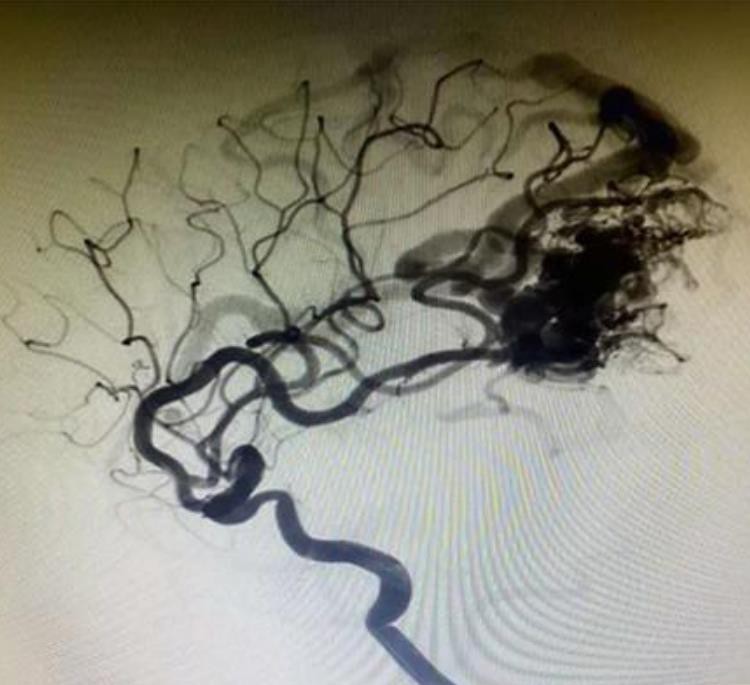

Kui laavaTmKoljusisesed aneurüsmid vedelemboolne süsteem on ühendust võtmas vere või mis tahes vesilahusega, selle pind tahkeneb kohe ja moodustab kaitsekile. DMSO emboolses aines lahjendatakse ja hajutatakse veres, nii et Evohiga mähitud tantaalpulber sadestub ja tahkub väljastpoolt seestpoolt. Samal ajal hajutatakse laava süsterõhu all kaugele. Lõpuks moodustab see emboliseerimisasendis käsnaemboolse keha.

LaavaTmAneurüsmi emboliseerimissüsteem on valmistatud mitteliibast materjalist, seega on see kateetri ohutum ja mitte-kleepuv.

See on ainulaadne madala viskoossusega valem, millel on täielik mudelite vahemik laava -12, laava -18 ja laava -34.

Sellel on parem dispersioon ja tungimine. ja see võib sügavalt tungida kahjustusesse ja jõuda distaalsesse laeva.

Tantalumipulber on peenemad, aeglasemalt sadestuvad ja konkurentidega võrreldes selgemalt radiograafia.